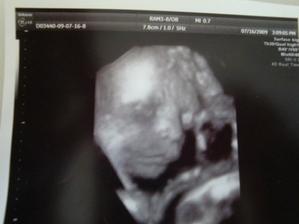

bara78

6. zář 2009

Bára a Tomík

Sedmý měsíc.

Tatínek nám zmizel, když jsem byla ve čtvrtém měsíci. Tak to musíme zvládnout sami.